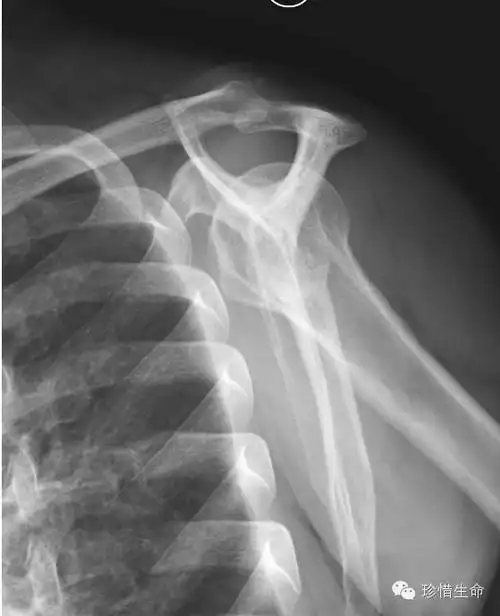

肩关节x线检查体位大全